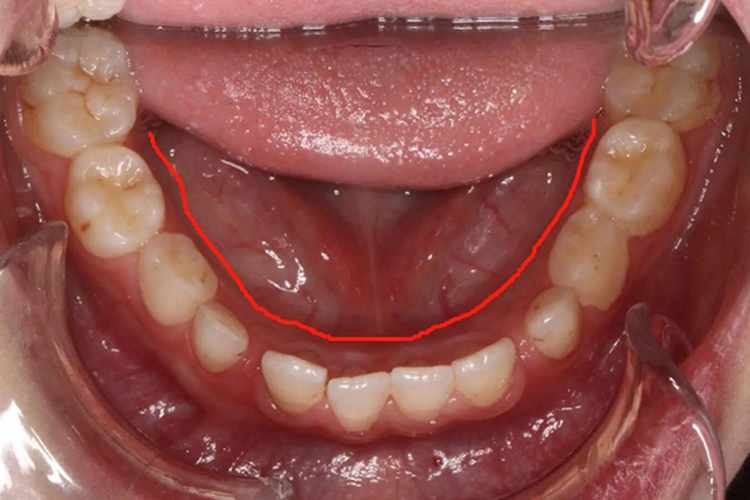

舌侧:舌侧通常是限于下颌,与颊侧相对,二者以牙齿为隔断,邻近舌黏膜一侧者称为舌侧,邻近颊黏膜一侧者为颊侧。

颊侧:即邻近口腔颊黏膜的一侧,在上颌,颊侧中间隔着牙齿与腭侧相对;在下颌,颊侧中间隔着牙齿与舌侧相对。

腭侧:腭侧限于上颌,与颊侧相对,二者以牙齿为界限。

在临床口腔舌侧、颊侧、腭侧,主要用于口腔病变的定位,比如邻近颊黏膜的牙龈即为颊侧牙龈,而邻近舌侧的牙龈即为舌侧牙龈。如果出现牙龈溃疡、红肿等病变,可明确定位病变的位置。牙齿亦是同理,在进行去腐充填或拔牙时,可根据具体的颊、舌、腭侧定位,分辨口腔内部方向,从而更加准确、方便地进行修复和治疗。